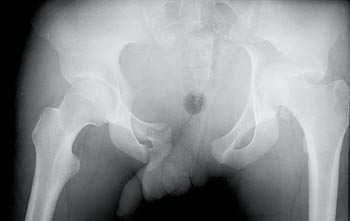

På akuttrommet var han fortsatt sirkulatorisk ustabil, til tross for massive infusjoner og blodtransfusjoner. Ved den initiale undersøkelse, utført av ortoped, ble bekkenet vurdert som stabilt. Det ble påvist tallrike andre ortopediske skader. Røntgen thorax og bekken ble tatt rutinemessig straks etter innkomst. Mens bildene ble fremkalt, ble pasienten undersøkt på nytt. Denne gangen fant man en stor diastase i symfysen. Røntgen av bekkenet viste betydelig diastase i symfysen, med avsprengt venstre acetabulum og venstre caput femoris luksert inn i bekkenet, i tillegg til flere andre frakturer (fig 1).

Bekkenfrakturen ble vurdert som sannsynlig årsak til pasientens ustabile sirkulasjon. Bekkenet og hele venstre underekstremitet ble stabilisert med ekstern fiksasjon, og blodtrykket stabiliserte seg. Seks måneder etter ulykken var pasienten oppegående, uten krykker, men med lett halting.